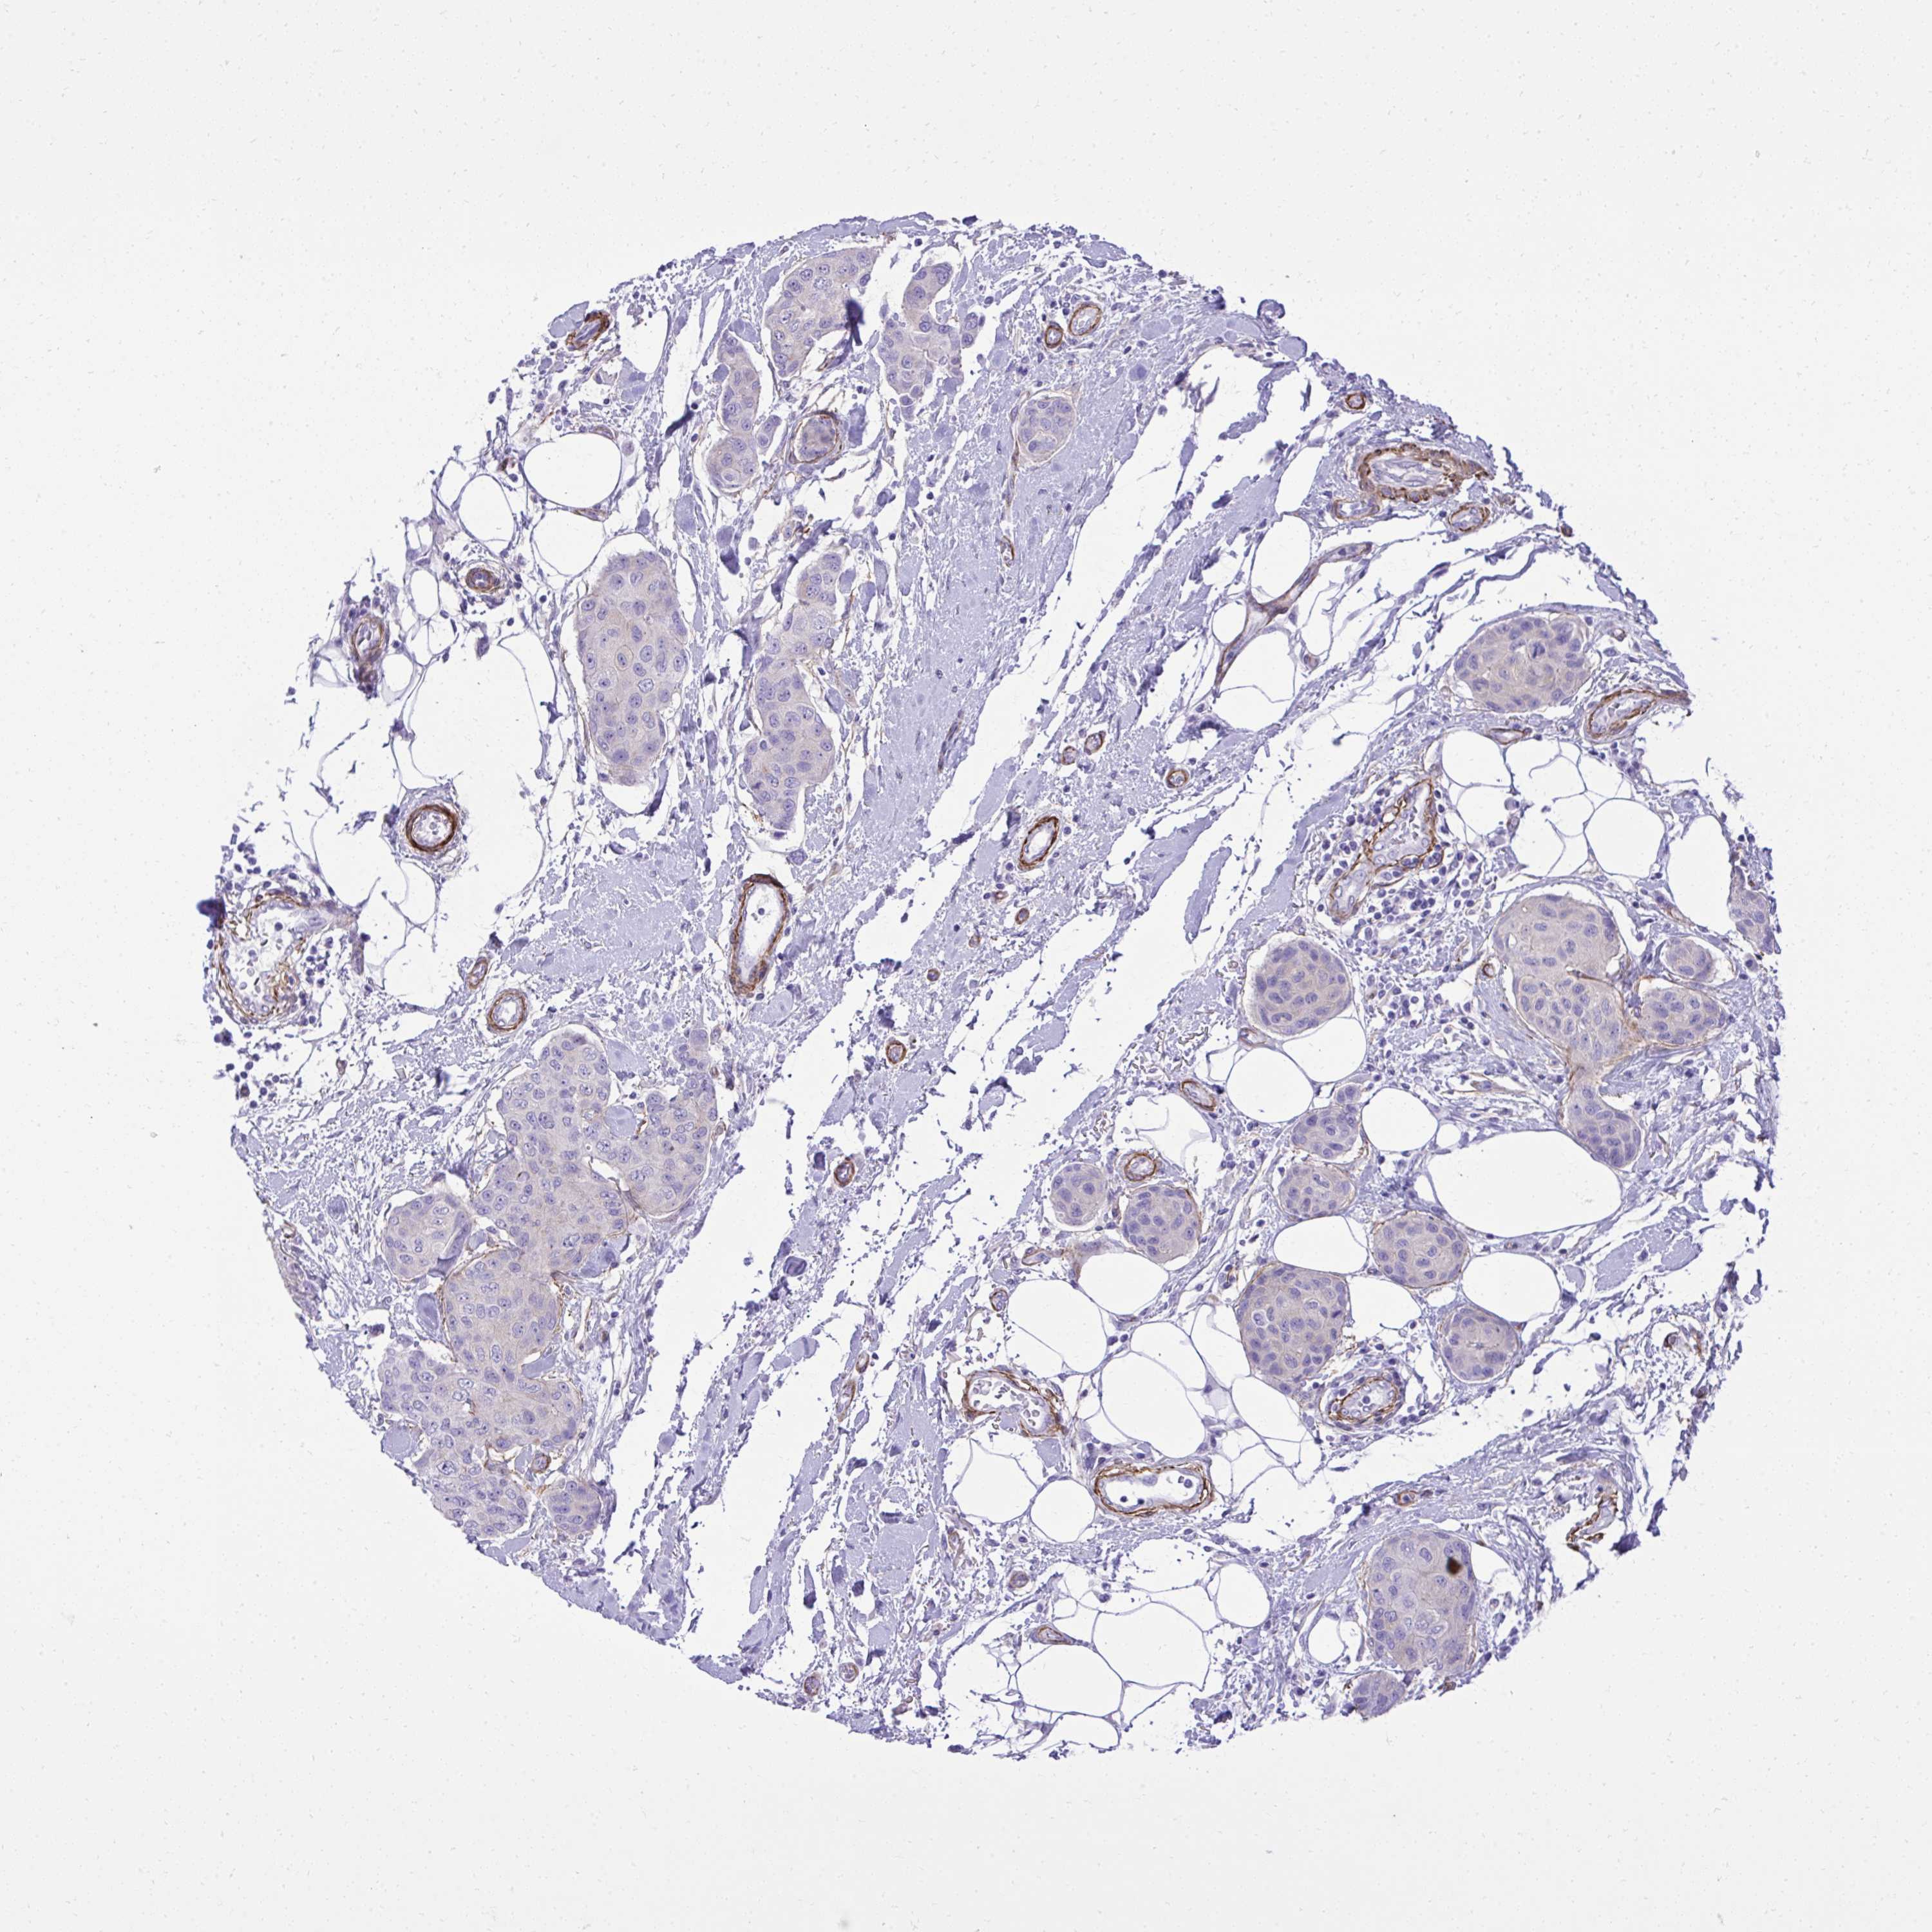

CANCER BREAST CANCER Show tissue menu

BRCA TCGA BRCA VALIDATION PROTEIN EXPRESSION

Breast cancer

Human cancer